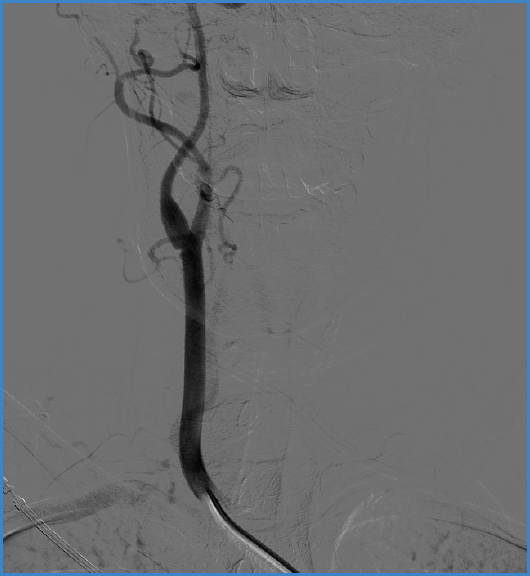

A 37-year-old woman with no significant medical-surgical history presented to the emergency department with a 3-hour history left hemiplegia. A brain CT scan revealed the presence of a right middle cerebral artery infarction, leading to emergency mechanical thrombectomy. During the procedure, an arteriography revealed the presence of a non-occlusive septum in the bulb segment of the right carotid artery, suggestive of a carotid web (Fig. 1). Cardiac origin was ruled out as she had sinus rhythm and an echocardiogram without abnormalities. A CT angiography was requested, confirming the diagnosis. A decision was made to perform right internal carotid endarterectomy (Fig. 2) with closure using an autologous saphenous vein patch. She was discharged after 72 hours uneventfully. At the 6-month follow-up, patency was observed, and there was no re-stenosis.

Figure 1. Arteriography image following an emergency thrombectomy procedure showing a septum in the right internal carotid artery suggestive of carotid web.